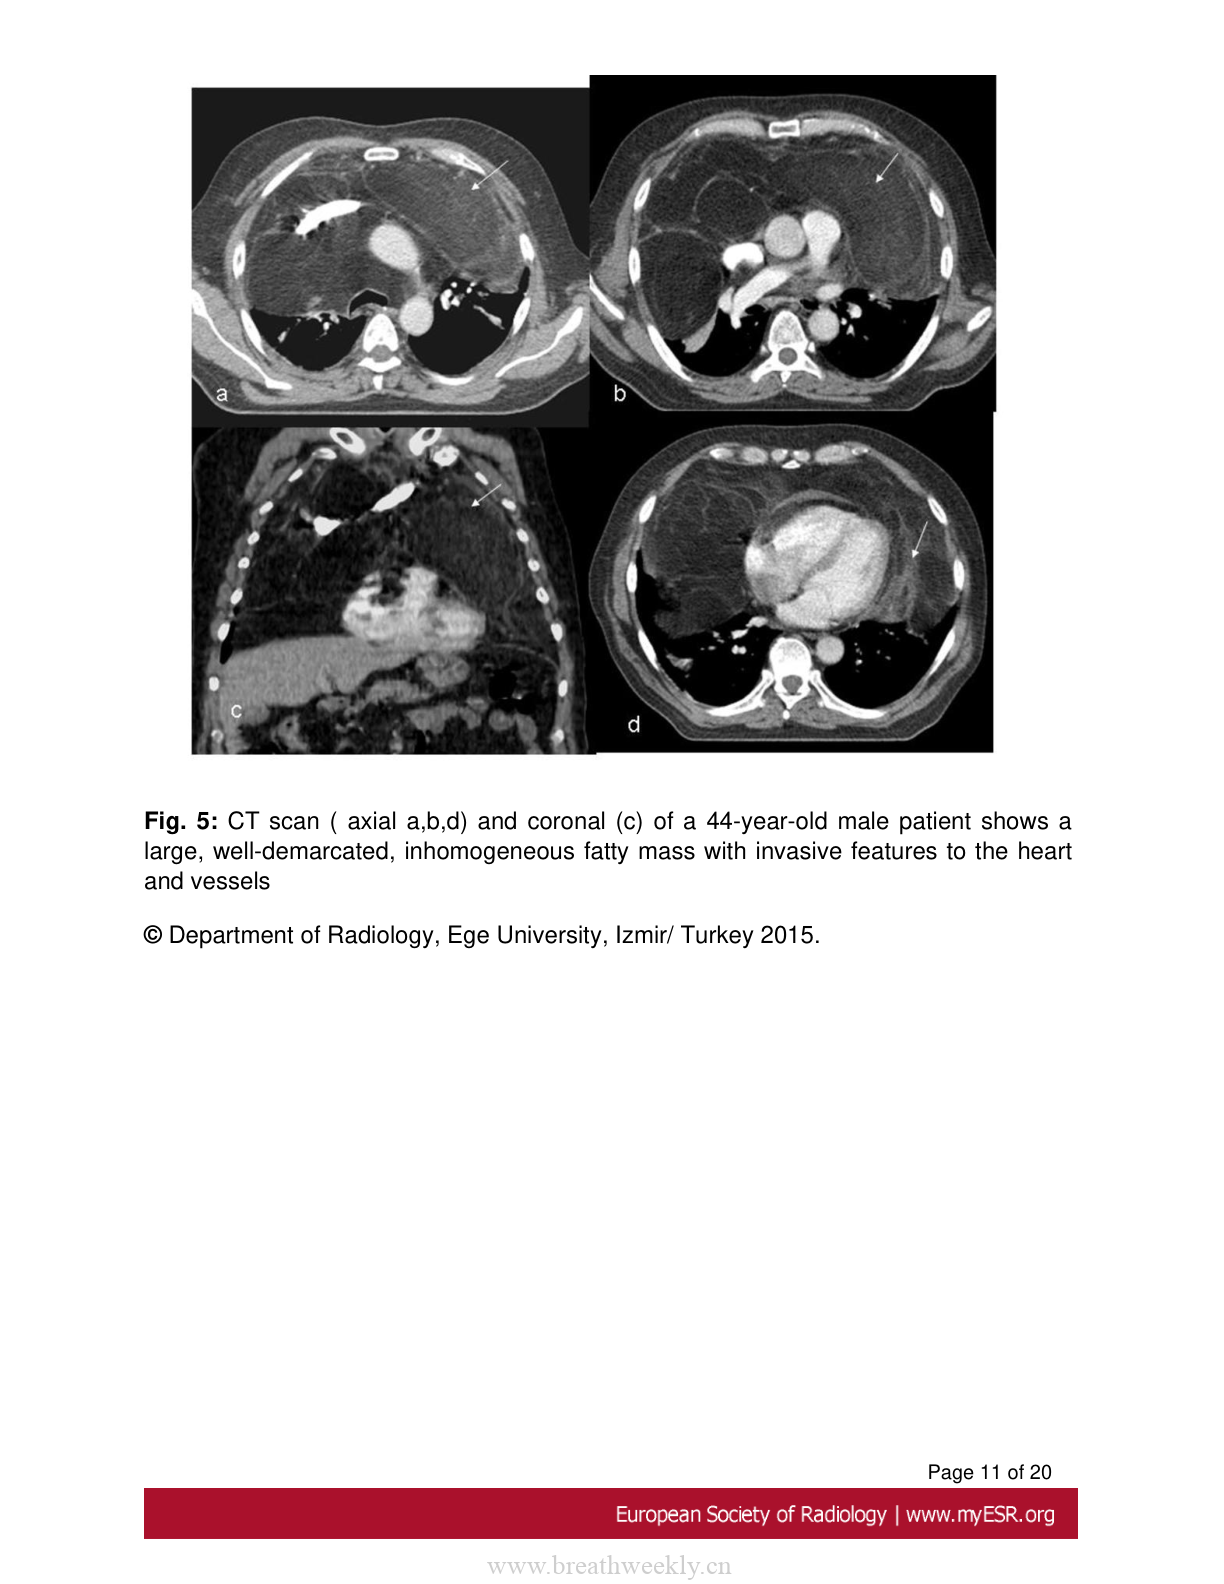

图5:纵隔脂肪肉瘤

44岁男性患者的CT扫描显示较大、边界清晰、不均匀的脂肪肿块,具有向心脏和血管侵犯的特征。